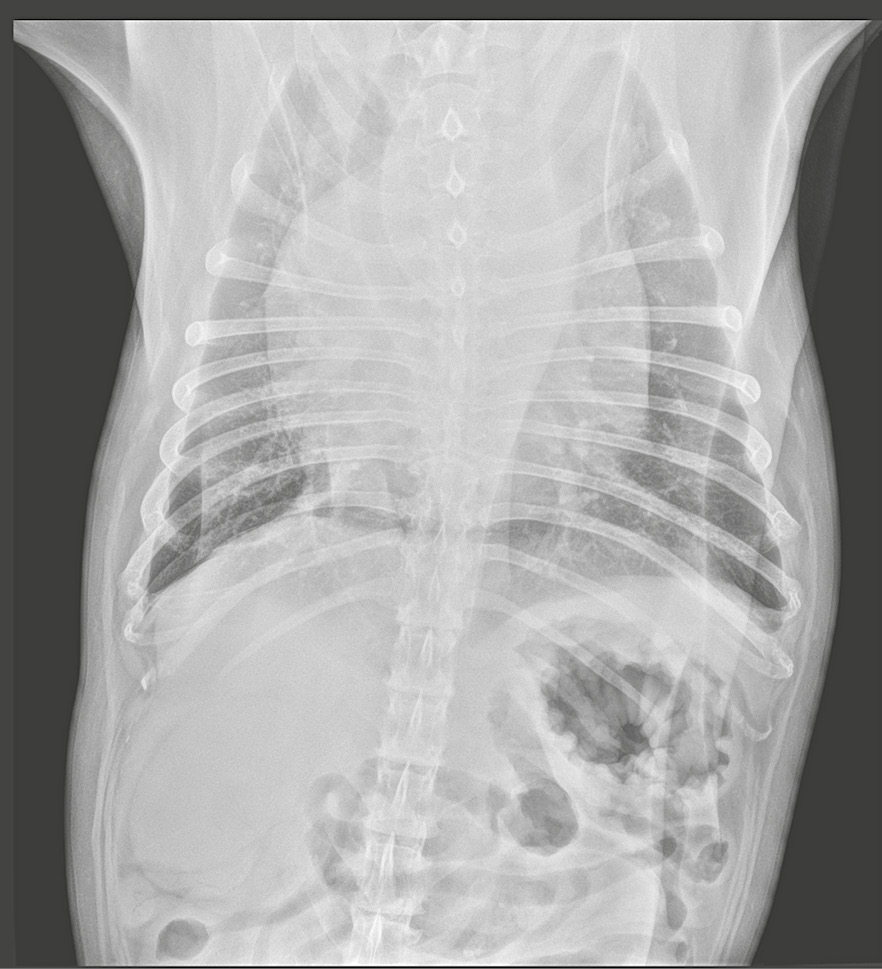

En las radiografías torácicas lo más relevante es la presencia de cardiomegalia con una silueta cardiaca de aspecto globoso, patrón bronco-intersticial difuso a nivel pulmonar y desplazamiento de la tráquea hacia el lado derecho (imagen 2).

Imagen 2. Radiografías latero-lateral derecha y ventro-dorsal del paciente en el momento del diagnóstico.